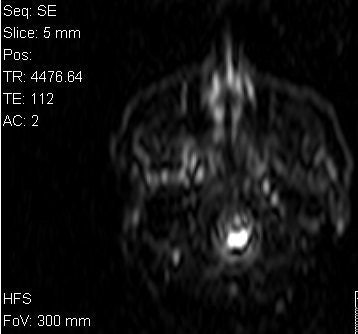

![]() |

Above, T1-weighted postcontrast axial image from the MRI series undergone by Dena Schlosser. Below, an axial diffusion-weighted image. Schlosser's neurologist examined Schlosser after her first trial and, based on the MRI exam, testified that midbrain injuries could cause visual hallucinations. Schlosser had previously told psychiatrists that she believed God wanted her to cut off her child's arms, as well as her own arms, legs, and head (Dallas Morning News, April 3, 2006). Images courtesy of David K. Haynes, Attorney at Law.